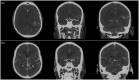

Purpose: This study compares computed tomography angiography-based collateral scoring systems in regard to their inter-rater reliability and potential to predict functional outcome after endovascular thrombectomy, and relates them to parenchymal perfusion as measured by computed tomography perfusion.

Methods: Eighty-four patients undergoing endovascular thrombectomy in anterior circulation ischaemic stroke were enrolled. Modified Tan Score, Miteff Score, Maas Score and Opercular Index Score ratio were assessed in pre-interventional computed tomography angiographies independently by two readers. Collateral scores were tested for inter-rater reliability by weighted-kappa, for correlations with three-months modified Rankin Scale, and their potential to differentiate between patients with favourable (modified Rankin Scale ≤2) and poor outcome (modified Rankin Scale ≥3). Correlations with relative cerebral blood volume and relative cerebral blood flow were tested in patients with available computed tomography perfusion.

Results: Very good inter-rater reliability was found for Modified Tan, Miteff and Opercular Index Score ratio, and substantial reliability for Maas. There were no significant correlations between collateral scores and three-months modified Rankin Scale, but significant group differences between patients with favourable and poor outcome for Maas, Miteff and Opercular Index Score ratio. Miteff and Maas were significant predictors of favourable outcome in binary logistic regression analysis. Miteff best differentiated between both outcome groups in receiver-operating characteristics, and Maas reached highest sensitivity for favourable outcome prediction of 96%. All collateral scores significantly correlated with mean relative cerebral blood volume and relative cerebral blood flow.

Conclusions: Computed tomography angiography scores are valuable in estimating functional outcome after mechanical thrombectomy and reliable across readers. The more complex scores, Maas and Miteff, show the best performances in predicting favourable outcome.